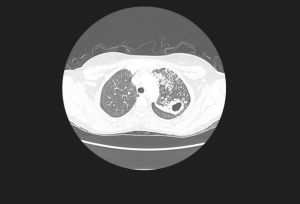

胸部CT

胸部CT掃描對發現常規胸片的隱匿區病變(肺尖、肺底、心臟後、脊柱兩側等肺部病變),了解肺門、縱隔淋巴結腫大情況及發現少量胸腔積液及少量氣胸有重要價值;增強CT通過不同時相可觀察選定部位的密度強化狀況,有助於疾病的診斷及鑑別診斷。氣管鏡檢查